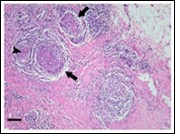

Core needle biopsy of idiopathic granulomatous mastitis enunciates multiple aggregates of non- caseating epitheloid cell granulomas within and encompassing breast lobules, constituted of epitheloid histiocytes, lymphocytes, neutrophils and multinucleated giant cells. Granulomatous inflammation is predominantly lobulo-centric. The inflammation is preponderantly composed of lymphocytes, plasma cells, epitheloid histiocytes, multinucleated giant cells and neutrophils. Neutrophils can configure micro-abscesses and encompass vacant micro-cystic cavities, morphological features which are in common with cystic neutrophilic granulomatous mastitis. Non specific lobulitis along with a lymphoid and plasma cell infiltrate accompanies the granulomatous inflammation. Necrosis is usually absent. Neutrophilic micro-abscesses can be accompanied by fistula formation 4, 5.

Fine needle aspiration can demonstrate a cellular exudate indicative of an abscess with an intense inflammatory infiltrate preponderantly composed of neutrophils. Ductal epithelial cells may be absent. Cytological examination delineates abundant and accumulated epitheloid histiocytes, neutrophils, lymphocytes with a variable degree of granuloma formation and an absence of necrosis 5.

Figure 7.Granulomatous mastitis with scattered epitheloid cells, neutrophilic exudate and aggregates of epithelod cells15.

Figure 8.Granulomatous mastitis with disseminated epitheloid cells admixed with neutrophils, lymphocytes and plasma cells 16.